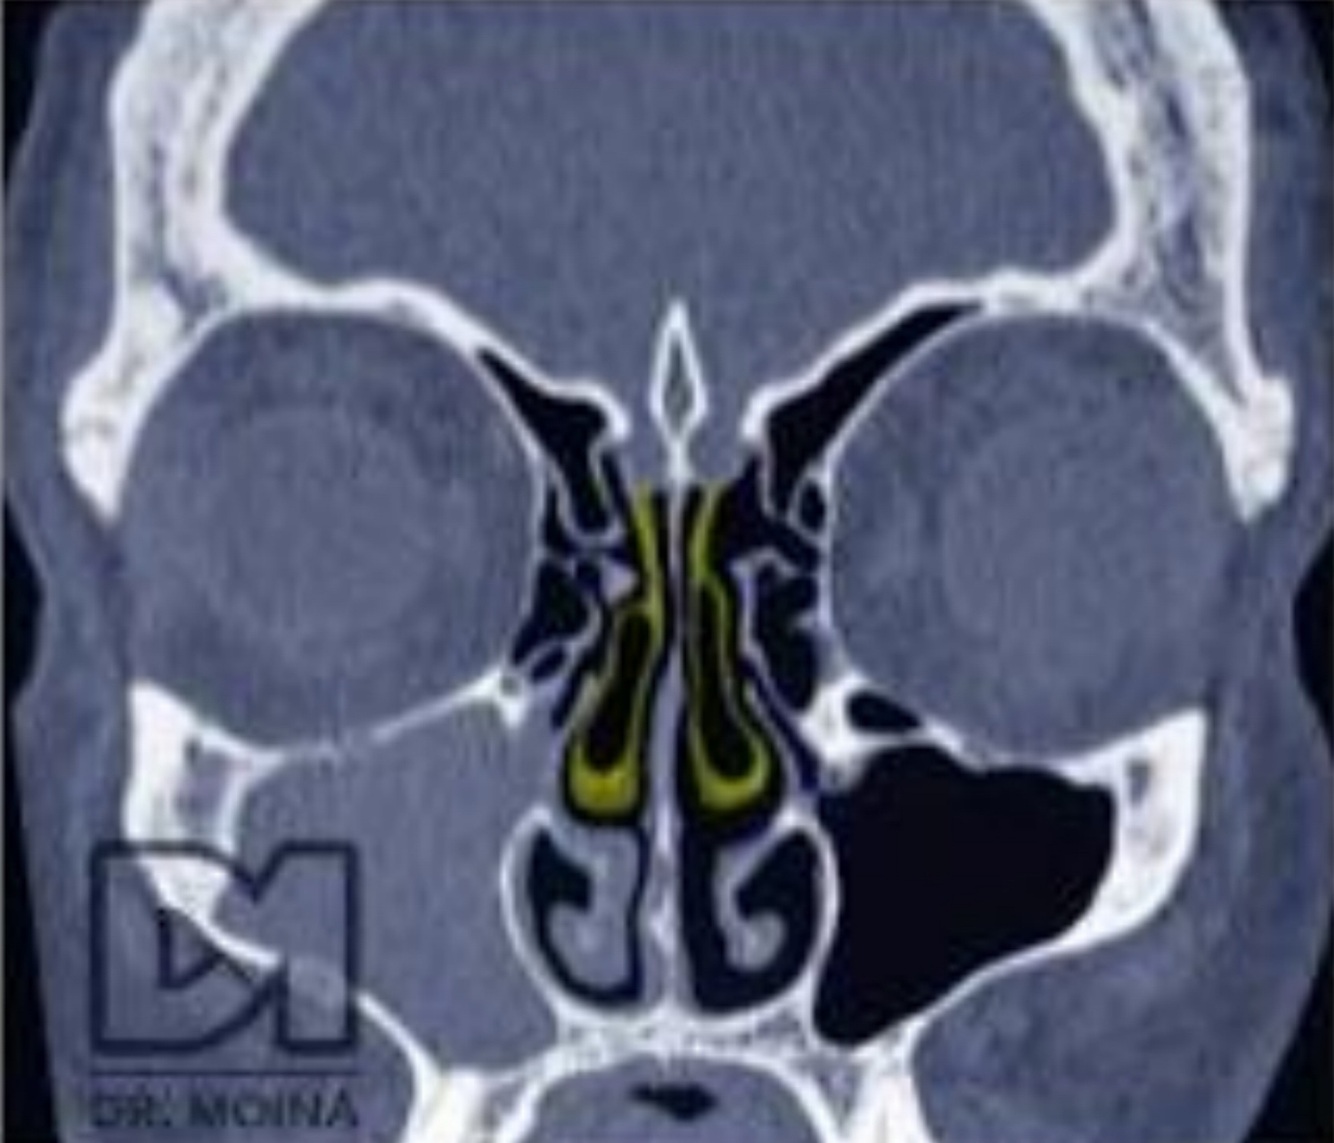

¿Qué es esto?

Desviación septal